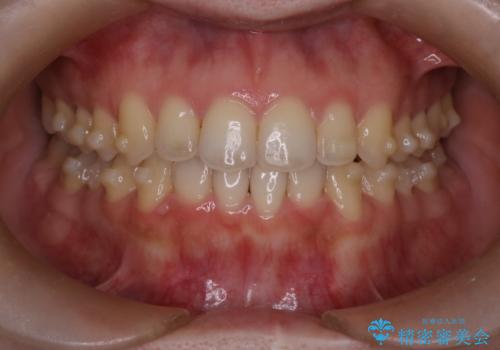

【インビザライン】オープンバイトを治したい

- 前歯の凸凹を主訴に来院された患者様です

骨格性の下顎前突傾向もあったため、臼歯関係の遠心移動も行うことで綺麗な仕上がりで矯正を終了することができました。

遠心移動を行うことで期間はかかりましたが、良い状態で仕上がっています。